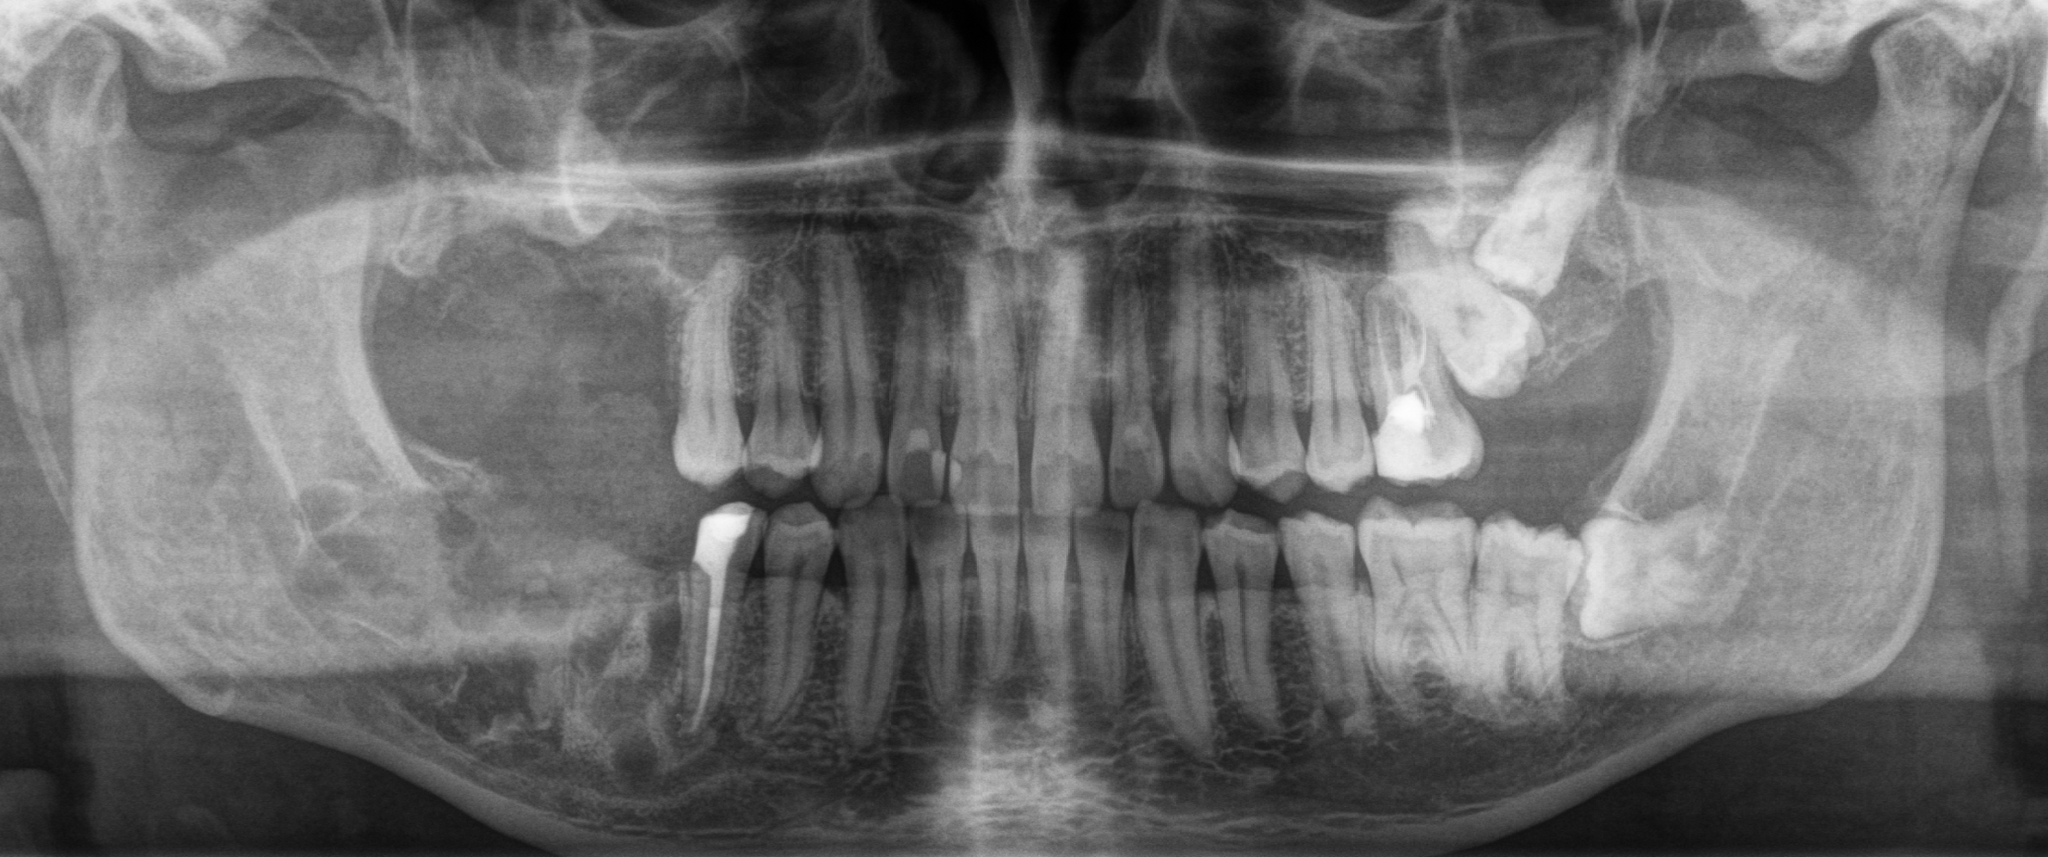

На панорамном снимке, сделанном после имплантации, хорошо видно, насколько высоко и неудачно она располагается:

В целом, каких-то явных изменений нет. В подтверждение тому, что это не один и тот же снимок, вы можете обратить внимание, что на имплантате уже установлена постоянная коронка.

Добрый вечер… А что это значит?... Прекрасно видно, что фолликулярная киста начала расти и оттеснять зуб мудрости дальше в пазуху, что несколько затрудняет его удаление. Блять, подумал я, надо было сразу удалять.

Контрольный снимок после удаления: